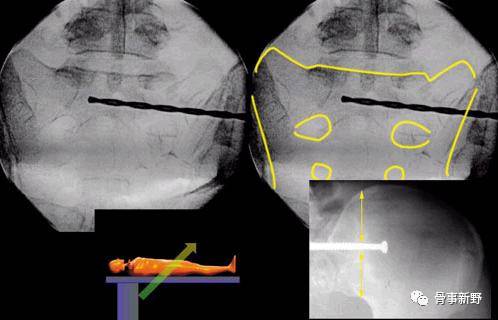

(1)体位:俯卧位(或者仰卧位)于透X线床上;必要时股骨髁上牵引。

(2)透视:C形臂放在患侧,术中透视骨盆正位、入口位、出口位及侧位。

(3)复位:通过牵引或者复位器械协助复位,复位骨盆后部,使坐骨大切迹和双侧骶骨翼、髂骨皮质投影重叠,克氏针临时固定髂骨翼和骶骨翼。

侧位:a1、a2代表双侧坐骨大孔;b1、b2:代表骶骨翼

(4)骶髂螺钉的定位:导针进针点在髂后上、下嵴之间,髂后上嵴外约2横指、坐骨大切迹上方2横指。透视确认入针点,正位、入口位及出口位满意后(在正位图像中导针尖部位于在S1椎体阴影中,出口位导针指向S1椎体中间1/3份,导针位于S1椎体上终板附件的骨质最厚处)。打入导针到中线,一共穿过3层皮质骨,透视位置确认后进行钻孔。